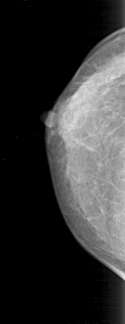

D_4165_1.RIGHT_CC

RIGHT_CC LINES 4201 PIXELS_PER_LINE 1621 BITS_PER_PIXEL 12 RESOLUTION 43.5 NON_OVERLAY